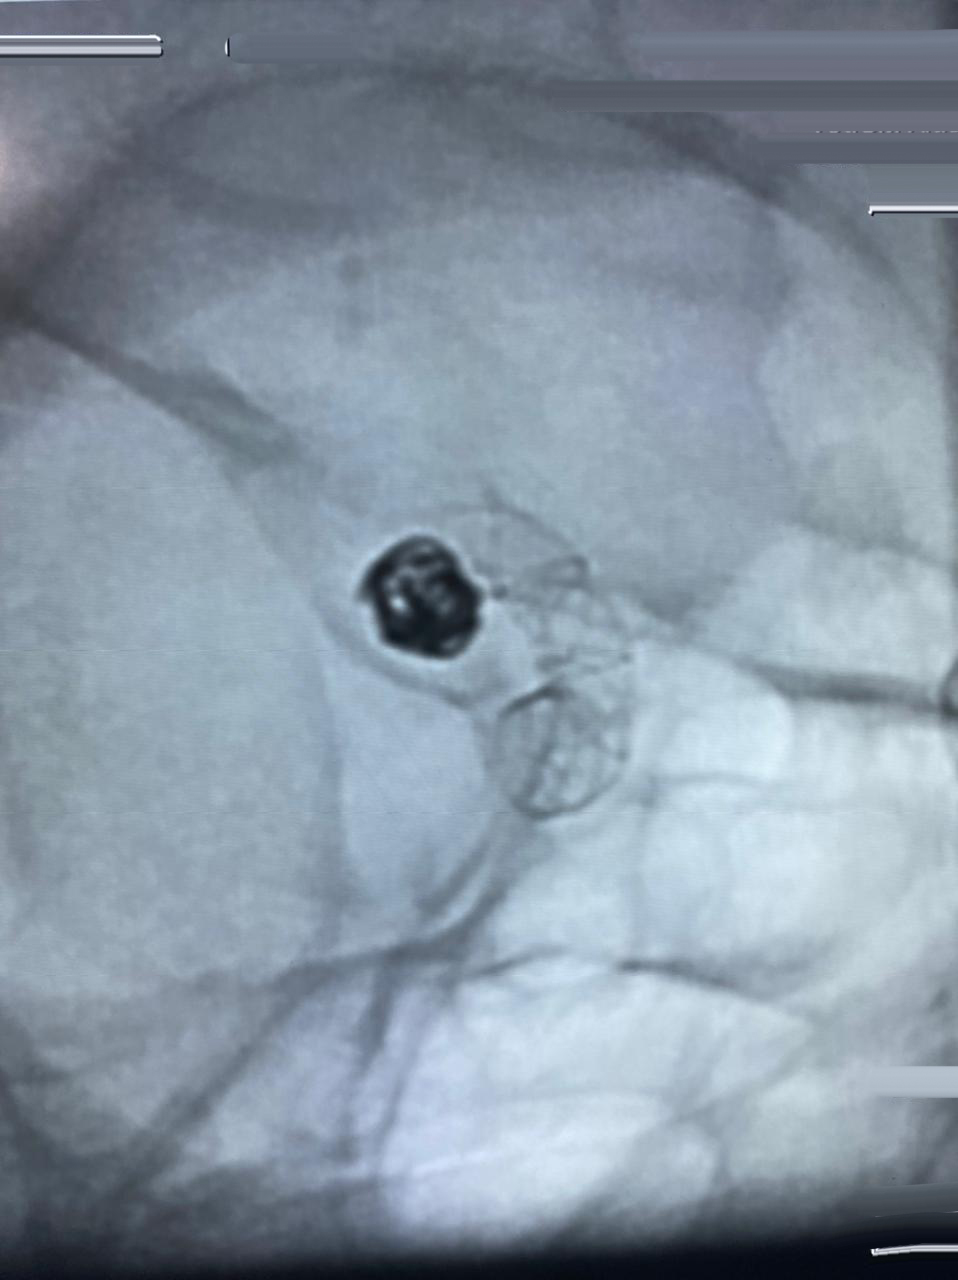

HCorBJ realiza procedimento de Embolização de Aneurisma Cerebral

O procedimento de Embolização de Aneurisma Cerebral é realizado no Setor de Hemodinâmica, sob anestesia geral, com um aparelho de imagem de última geração. O tratamento endovascular, é uma opção minimamente invasiva para as doenças cerebrovasculares.

“O primeiro caso de Embolização de Aneurisma Cerebral em Ponta Grossa, com stent diversor de fluxo, foi realizado no Hospital do Coração Bom Jesus em dezembro de 2018, o HCorBJ tem estrutura excelente para isso, tanto para realização do método, quanto no atendimento pós- operatório dos pacientes na Unidade de Terapia Intensiva (UTI) e enfermaria, com equipes altamente especializadas”, ressalta Sabatini.

A última intervenção realizada no HCorBJ, contou com a participação do Dr. Gelson Luis Koppe, médico neurorradiologista intervencionista de Curitiba.